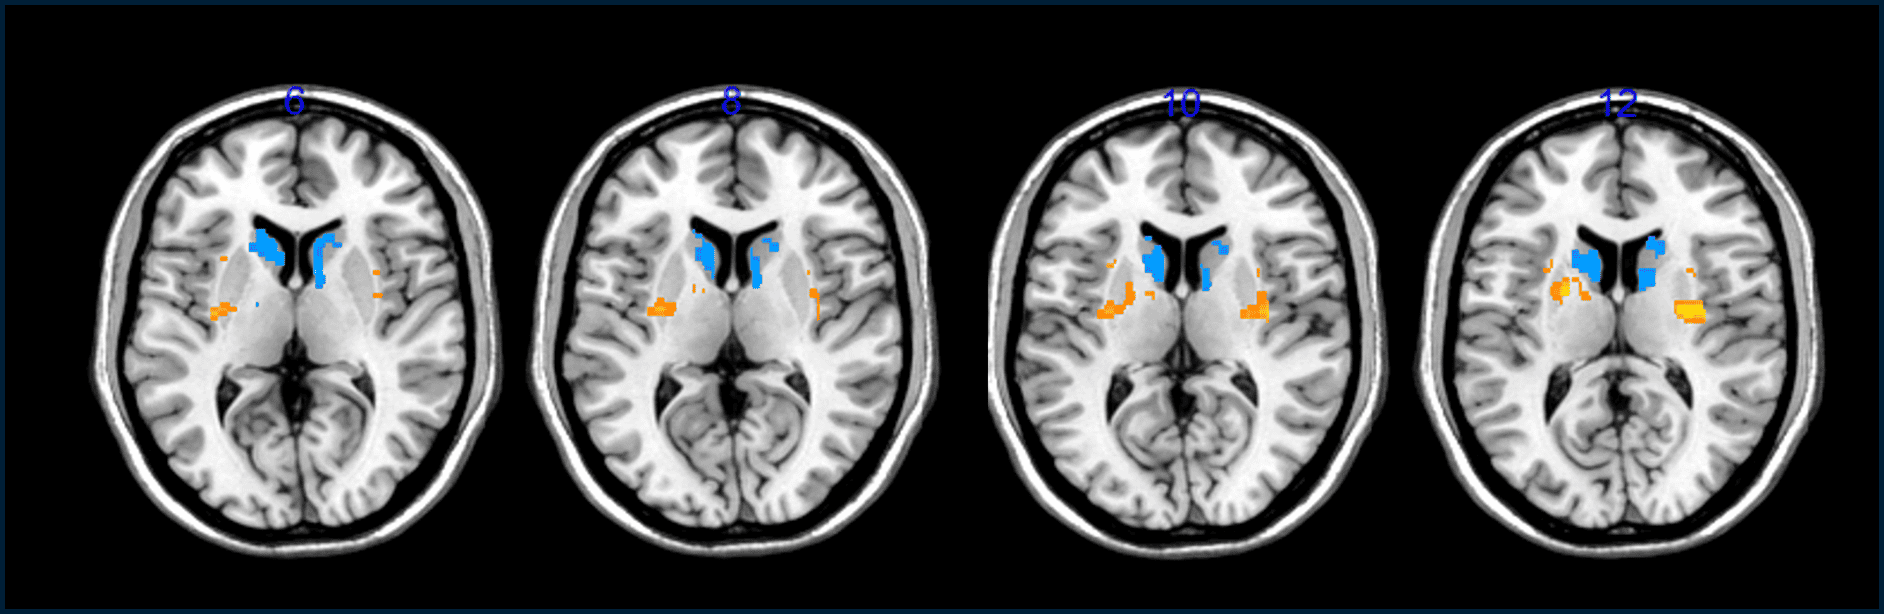

استُخلصت هذه المؤشرات التي تبيّن أن عمليات الزرع كانت مفيدة من عمليات مسح الدماغ التي بيّنت زيادة في عدد الخلايا التي تفرز الدوبامين في أدمغة المرضى وانخفاضاً في "فترة العجز"؛ وهي عدد الساعات اليومية التي يشعر فيها المتطوعون بأنهم عاجزون بسبب الأعراض التي يعانونها.

يتحقق الباحثون من بقاء الخلايا المزروعة على قيد الحياة من خلال حقن مادة مشعة سلف للدوبامين ثم مراقبة معدل امتصاصها في أدمغتهم باستخدام ماسح التصوير المقطعي بالإصدار البوزيتروني؛ وذلك لأنهم لا يستطيعون رؤية هذه الخلايا مباشرة بمجرد زرعها في أدمغة المرضى. بالنسبة إلى باركر؛ لم تكن هذه النتائج رصينة للغاية، وهو يقول إنه "ما يزال من السابق لأوانه معرفة" ما إذا كانت الخلايا المزروعة نجحت في ترميم التلف في أدمغة المرضى.